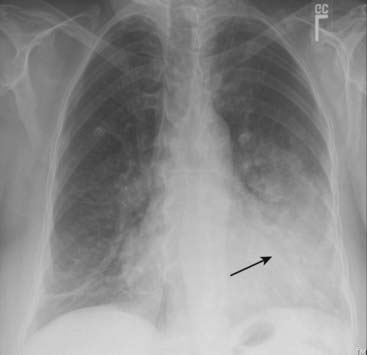

Figure 7-1 Left upper lobe pneumonia.

Several black, branching structures are seen in this upper lobe pneumonia (solid white arrows) that represent typical air bronchograms seen centrally in airspace disease in this patient with pneumococcal pneumonia. The disease is homogeneous in density, except for the presence of the air bronchograms. Because this is airspace disease, its outer edges are poorly marginated and fluffy (dotted white arrow).

image

Figure 7-2 Lingular pneumonia.

Airspace disease is present in the lingular segments of the left upper lobe. The disease is of homogeneous density. The disease is in contact with the left lateral border of the heart, which is “silhouetted” by the fluid density of the consolidated upper lobe in contact with the soft tissue density of the heart (solid black arrow).